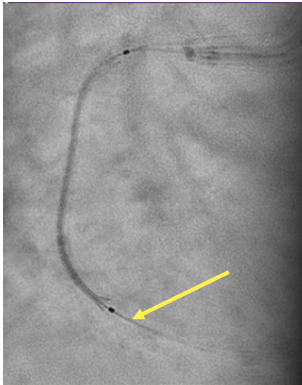

In view of this complication and the clinical instability of the patient, extraction of the device with a coronary snare was attempted but was unsuccessful (Figure 3). The access route was then changed to the femoral artery using an Amplatz left 6F catheter, and a Sion guidewire was advanced to the distal segment of the right coronary artery with the support of a 135-cm FineCross microcatheter (Terumo). This was followed by dilatation using a Sapphire II PRO balloon (OrbusNeich) (Figure 4) with catheter extension and anchoring of the balloon until 2 new everolimus-eluting stents (2.5 x 40 mm and 3.0 x 15 mm) could be advanced (Figure 5). Upon post-dilation of the noncompliant balloon, the previous stent and ballon were successfully crushed, obtaining a good final angiographic result (Figure 6). The procedure was completed with intracoronary optical coherence tomography, which confirmed adequate stent expansion and apposition, as well as the crushing of both the stent and the previous balloon (Figures 7-11).